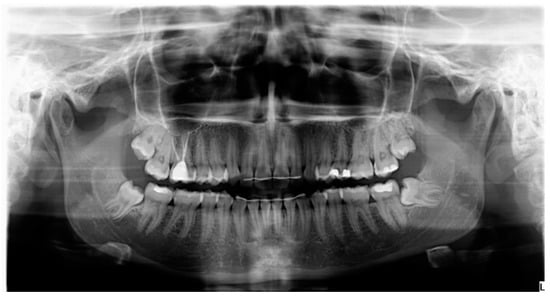

- Probing depth was measured 3 and 6 months after surgery at the DV, DM and DL points on the distal aspect of the second molar as shown in Figure 3.

- Bone density, the degree of corticalization, and crestal bone height maintenance were measured 6 months after surgery on CBCT sagittal slices in all patients (Figure 6), using the same equipment (Newtom VGI evo, QR srl-Verone, Italy).